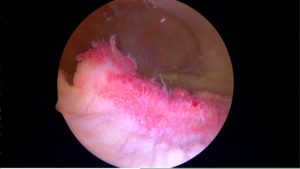

image

Inflamed synovium: notice how red and “angry” it looks.

The second issue that can cause knee pain and swelling is the synovium. The synovium is the lining of the knee joint. It’s like a balloon that surrounds the bones of the knee. There are many nerve endings there. Synovitis is inflammation of that lining tissue or synovium.

Synovitis can be a very painful process. As an aside, for people with pain due to synovitis that does not respond to time, ice, heat, medications, ,etc– a relatively new procedure called a genicular artery embolization has shown significant promise at eliminating that cause of knee pain. You can read about a knee embolization procedure here.